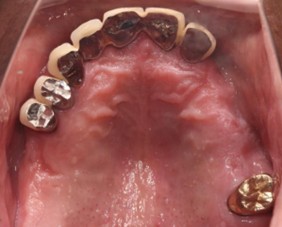

70代 女性

治療前

治療後- リスク・副作用

(薬・注射・レントゲン・ソケットリフト骨造成・サージカルステント・CT・データ分析) - 年齢/性別

- 70代/女性

- 患者の具体的な症状

- 右上56欠損のため義歯を使用していたが不安定で十分噛めないため、インプラント治療を希望

- 検査方法

- コーンビームCT、レントゲン撮影

- 診断結果

- 右上56欠損

- 治療詳細

- 右上56部、コーンビームCTによる画像診断で垂直的な骨高、骨密度の不足のため、ソケットリフトによる骨再生治療とインプラント埋入2本を同時にショートインプラントを用いて行った。

- 通院回数

- 7回

- 治療期間

- 7か月